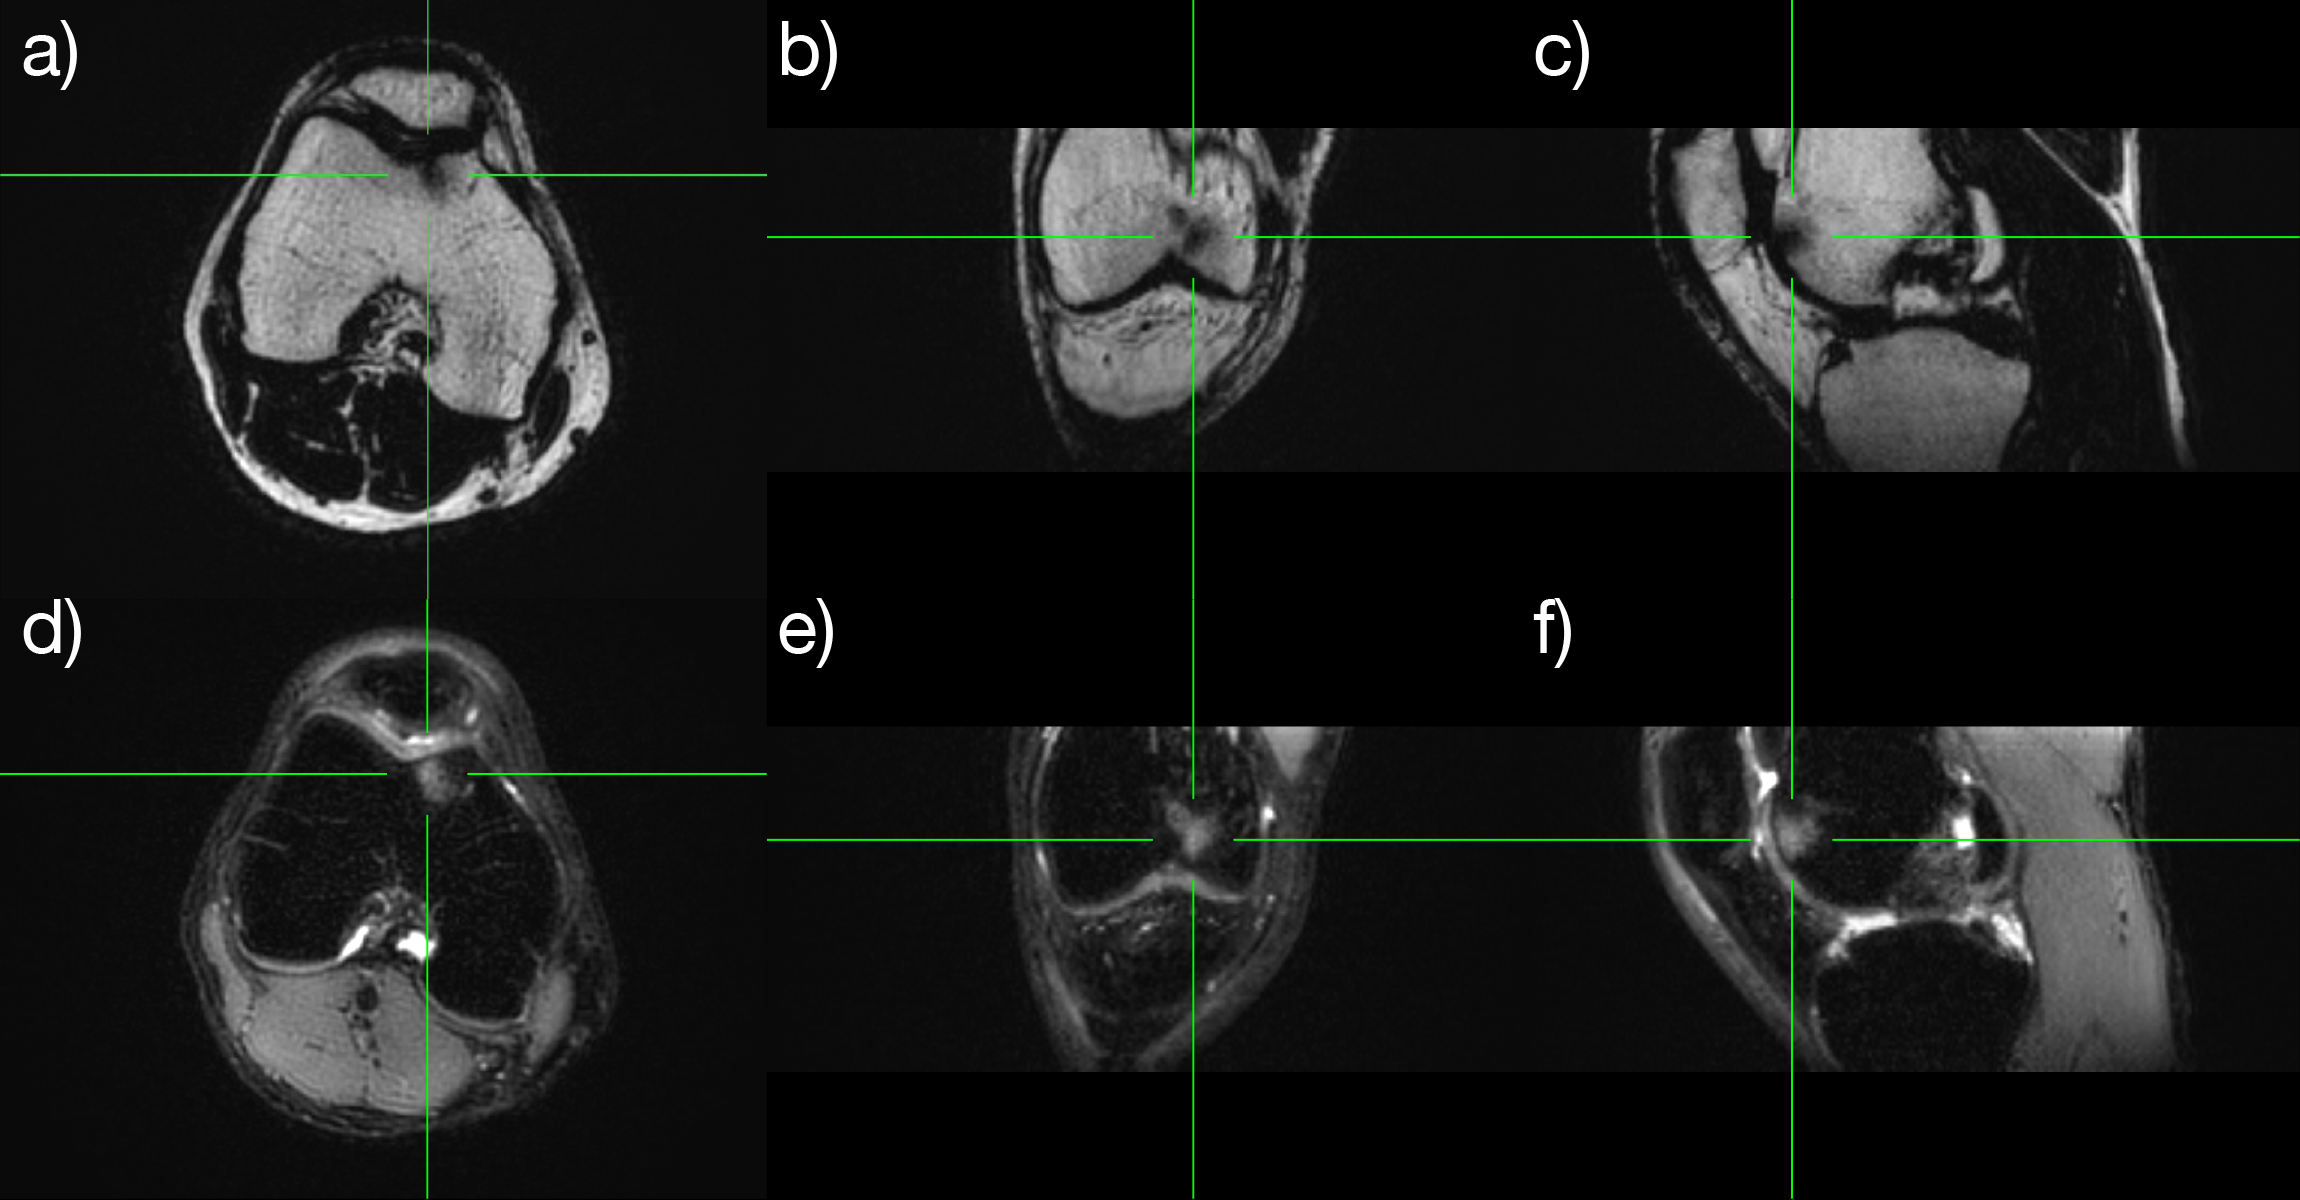

Figure 2: Right knee. Fat/water separated pseudo 3D PROPELLER images with coronal and sagittal reformats. Displaying the fat images in the top row (a-c) and the water images in the bottom row (d-f). Green lines show the positions of corresponding image planes. The bone marrow edema (pointed out by the green lines) is bright on the water images and dark on the fat images.